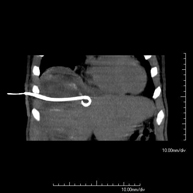

- Drenaje abdominal guiado por TC (abscesos, colecciones)

Consiste en colocar un catéter de drenaje sobre una colección líquida localizada en la cavidad abdominal, con la intención de vaciar el máximo posible dicha colección. El paciente deberá mantener el drenaje algunos días, normalmente hasta que no sea productivo. A menudo se realiza bajo sedación, con la ayuda del equipo de anestesia. Todo el procedimiento se realiza controlado con imágenes obtenidas por Tomografía Computarizada (TC) en varios momentos de la prueba mediante el empleo de Fluoroscopia-TC. Tras la prueba, el paciente permanece hospitalizado. Es necesario aportar pruebas de coagulación antes de la prueba.

- Drenaje abdominal guiado por TC

Consiste en colocar un catéter de drenaje sobre una colección líquida localizada en la cavidad abdominal, con la intención de vaciar el máximo posible dicha colección. El paciente deberá mantener el drenaje algunos días, normalmente hasta que no sea productivo. A menudo se realiza bajo sedación, con la ayuda del equipo de anestesia. Todo el procedimiento se realiza controlado con imágenes obtenidas por Tomografía Computarizada (TC) en varios momentos de la prueba, mediante el empleo de Fluoroscopia-TC. Tras la prueba, el paciente permanece hospitalizado. Es necesario aportar pruebas de coagulación antes de la prueba.